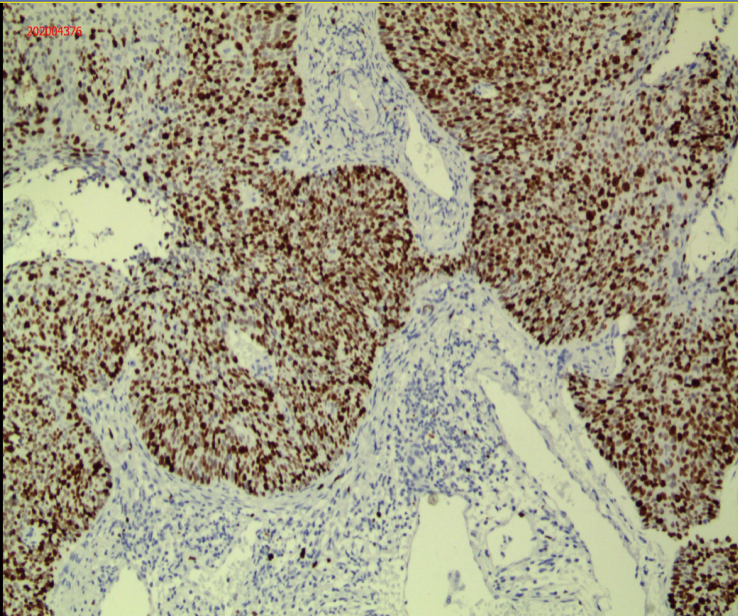

▲宫颈活检病理显示刘女士患有非角化型鳞状细胞癌